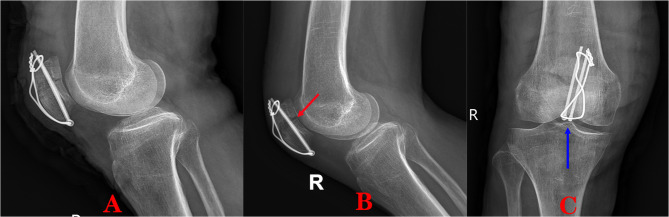

Methods: Fourty-two patients with transverse patellar fractures participated in this study, twenty of whom underwent minimally invasive surgery and twenty-two underwent open surgery. In the minimally invasive group, intraoperative tension band internal fixation was performed using Nice knot assisted reduction. Postoperative knee pain, knee mobility, operative time, complications, number of intraoperative C-arm fluoroscopy scans, length of hospital stay (in days), and Bostman score were recorded for each patient in both groups.

Conclusions: It has been demonstrated that using the Nice knot in the minimally invasive treatment of transverse patellar fractures improves the reduction effect and decreases the incidence of iatrogenic fractures.Patients who underwent minimally invasive surgery experienced early postoperativepain reduction, improved knee range of motion, improved Bostman scores, early postoperative, discharge and incidence of complications.